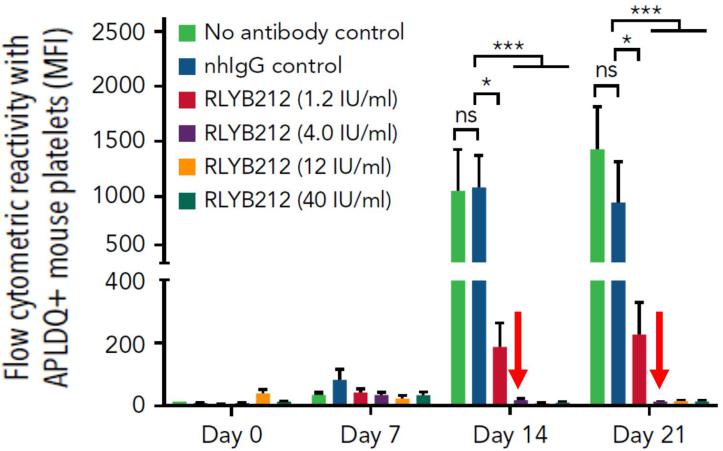

A mouse model of FNAIT has been created in which the amino acids comprising the HPA-1a antigen are reconstituted in the mouse gene. These transgenic mice (referred to as APLDQ mice based on the amino acid changes) recapitulate multiple aspects of FNAIT. Administration of anti-HPA-1a antibodies to APLDQ mice leads to destruction of APLDQ platelets and severe thrombocytopenia. Injection of platelets from APLDQ mice into wild-type mice can induce an HPA-1a specific immune response. Finally, wild-type female mice pre-immunized with APLDQ platelets, when bred with APLDQ male mice, give birth to severely thrombocytopenic pups, many of which exhibit an accompanying bleeding phenotype. Treatment of these pregnant female mice with IVIG resulted in lowering the level of anti-APLDQ antibodies in the fetus and a reduction in thrombocytopenia.

In a prophylactic treatment model, a single large bolus intravenous injection of 1 x 108 APLDQ platelets (equivalent to about one-sixth of the total blood volume in the host) was administered to wild-type mice. At a dose of 0.4 µg (yielding a peak concentration of approximately 0.2 µg/ml), RLYB212 was able to drive rapid and complete elimination of APLDQ platelets, as shown in the first graph below, and prevent a host antibody response, as shown in the second graph below. Also shown in the graphs below, this dose correlates to a concentration of RLYB212 projected to bind approximately 10% of the HPA-1a antigen present on the transfused APLDQ platelets. Thus, the approximately 10% receptor binding is sufficient to clear platelets and prevent alloimmunization in the mouse model.

| | | | | |

RLYB212 Induced Rapid Elimination of APLDQ Platelets | RLYB212 Prevented the Development of Antibodies to APLDQ Platelets |